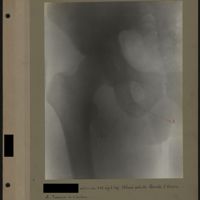

0012 - Page 8 - [Radiographie de la hanche et du fémur]0012 - Page 8 - [Radiographie de la hanche et du fémur]

0062 - Page 58 - [Radiographie de la hanche]0062 - Page 58 - [Radiographie de la hanche]

0085 - Page 81 - [Radiographie de la hanche et du fémur]0085 - Page 81 - [Radiographie de la hanche et du fémur]